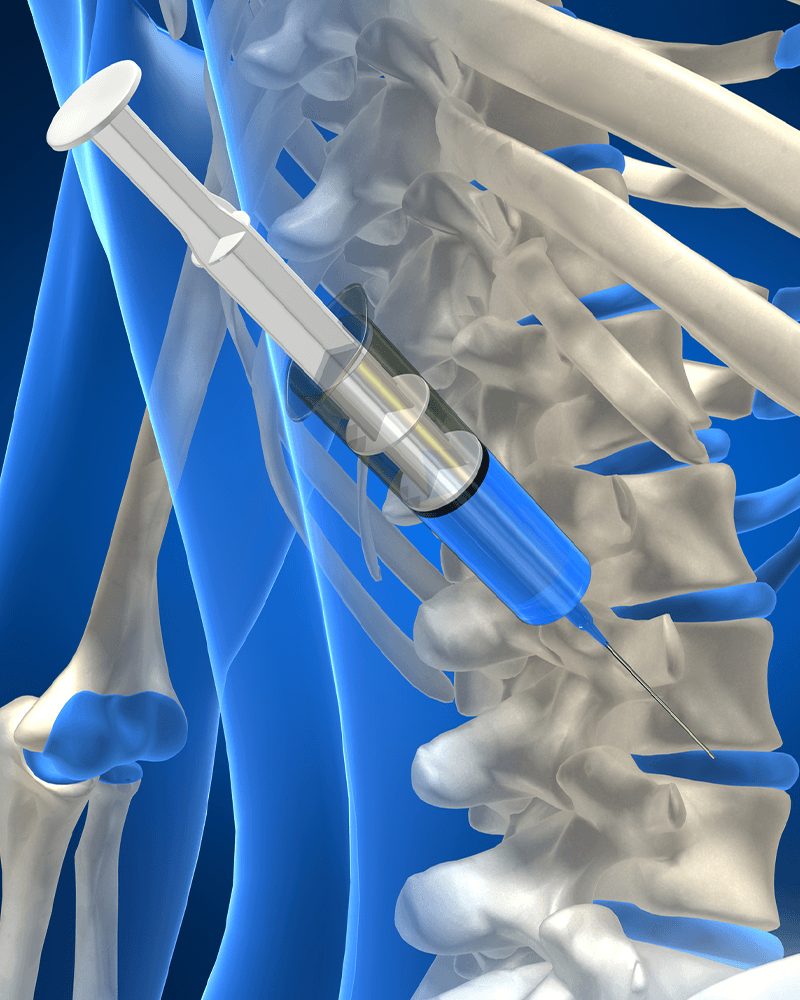

비수술 치료부터 고난이도 수술까지!

수술을 잘하는 의사가 비수술 치료도 잘합니다.

- 고난이도 척추 수술 및 시술 20,000여회 집도

- 척추신경주사 및 관절주사 40,000여회 시행